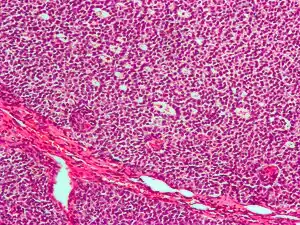

| Micrograph of a granulosa cell tumour, a type of sex-cord–gonadal stromal tumour. H&E stain. | |

By prevalence